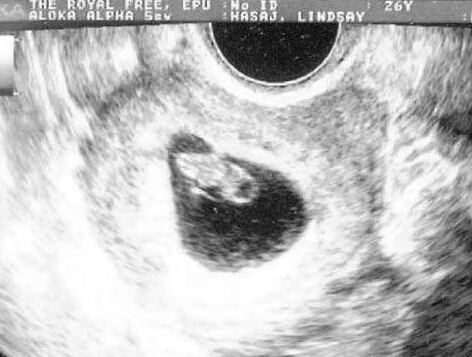

方法四:B超监测排卵法

所有测排卵的方法中,最为准确的就是B超监测法。不仅可以得知卵泡发育的好坏状况及卵泡是否老化,还可以观测子宫内膜的情况,动态观察卵泡生长发育成熟情况,准确预测排卵。一般在月经周期第10天开始监测,观察卵泡直径的变化。在排卵前4天卵泡直径平均每日约增加3毫米,到排卵前卵泡成熟,直径增加为17~25毫米,排卵后卵泡消失,当最大的卵泡消失时,提示发生排卵。

西安安琪儿妇产医生提醒:B超监测排卵,应该坚持一个监测周期,可了解卵泡有无持续发育。去正规的医院尽量找固定的医生监测,不同的医生,判断可能会出现差异。

推荐指数:★★★★★

西安安琪儿妇产医生建议女性朋友们来医院做阴道B超检测排卵,利用阴式B超检测排卵是直接、准确的方法。不仅能够准确测定卵泡的大小,推定排卵的日期,提高受孕的机率;而且医生还会结合检查结果针对不同备孕女性的身体状况,妇科疾病提出专业的受孕指导和治疗方案。一些妇科疾病也是影响女性受孕的一个因素,发现了要尽早治疗。